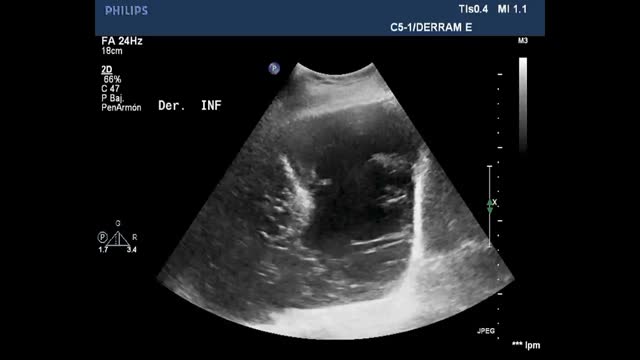

Pleural effusion (PE)Ultrasound assesses the volume (detecting millimetric magnitudes) and the characteristics of PE, guiding the site of puncture for evacuation of the effusion when needed. For this purpose, we ideally use a low-frequency convex probe (2.5-5 Hz), which sacrifices resolution in favor of greater ultrasound wave penetration capacity, reaching more in depth and visualizing the diaphragm and liver or spleen, and their relation to the lung parenchyma.

With the patient in the supine position, we place the probe on the mid-axillary line and locate the fundamental reference of the study: the diaphragm. All anechoic images above the diaphragm correspond to the chest cavity (pleural fluid). In contrast, such images located below the diaphragm correspond to the abdominal cavity (ascitic fluid)(Video 10).

Ultrasound signs related to pleural effusionPleural effusion is a genuine image, not an artifact. It is classically defined as an anechogenic component. The appearance of PE in critical patients is not always as described, however, since there may be coexisting hemothorax, complicated effusion and empyema, which are characterized by different degrees of echogenicity.

In terms of ultrasound exploration, PE is defined by the following signs:

- a

Quad sign (Suppl. Fig. 8): This is a static sign defined by a quadrilateral image with regular margins. The upper margin corresponds to the parietal pleura, the lower margin to the visceral pleura, and the lateral margins correspond to the shadows of two consecutive ribs.

- b

Sinusoid sign (Suppl. Fig. 8) (Video 11): This is a dynamic sign. In M mode it manifests as a sinusoid, reflecting the variation of the interpleural distance with the respiratory movements. In this regard, the distance is shorter during inspiration, while in expiration the two pleural layers are more separated. When the fluid is more viscous or shows septation, this sign may be absent.

Minor PE (almost not observable in the CT scan) is detected by ultrasound as the “quad sign” and “sinusoid sign” – hence the importance of evaluating them in the context of a thoracic ultrasound study.

- c

Jellyfish sign: In the presence of a significant amount of intrapleural fluid, the underlying lung collapses, and the parenchyma exhibits a static air bronchogram. The atelectatic lung is contained within the PE and in the lower zone appears floating freely within the fluid, generating the characteristic movement of the jellyfish sign (Video 12).

To date, no concrete ultrasound sign has been established that can firmly distinguish between transudate and exudate. What we can do, however, is interpret the appearance of the fluid. In this regard, we can observe simple PE (generally anechoic), complex septate or non-septate PE (generally corresponding to exudate)(Video 13), and diffuse echogenic fluid (often associated with the presence of fibrin or proteins). The plankton sign (Video 14) in turn consists of an echogenic dotted pattern floating freely in the PE. Although it may cause us to suspect a complicated PE, such differentiation cannot be firmly established.